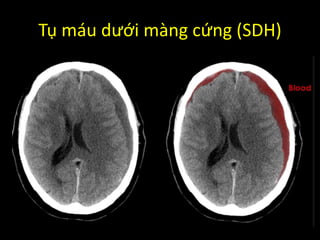

Tụ máu dưới màng cứng (SDH)

Phân biệt EDH và SDH?

SDH

• Bờ nhu mô không đều

(crescent moon)

• Không bị giới hạn bởi

các khớp xương sọ

Tụ máu dướimàng cứng (SDH)

Phân biệt EDHvà SDH? EDH • Khối 2 mặt lồi (eye shape) • Bị giới hạn bởi các khớp xương sọ SDH • Bờ nhu mô không đều (crescent moon) • Không bị giới hạn bởi các khớp xương sọ